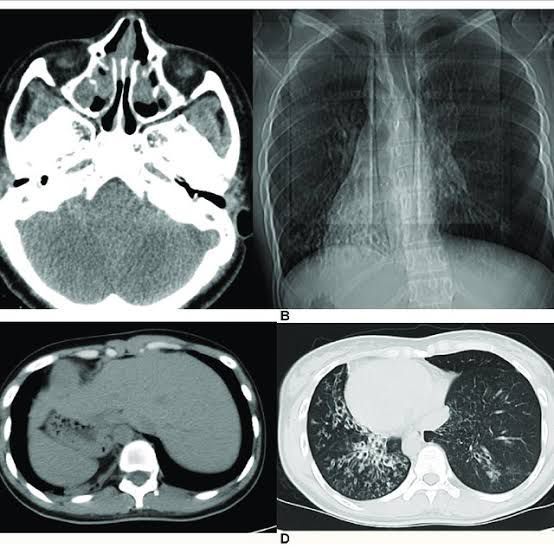

Kartagener syndrome treatment

Regular sinus washes. Regular ear canal washes. Steroids. Mucus thinners, called mucolytics. Antibiotics. Bronchodilators to relax lung muscles for easier breathing. Ear tubes. Speech therapy.